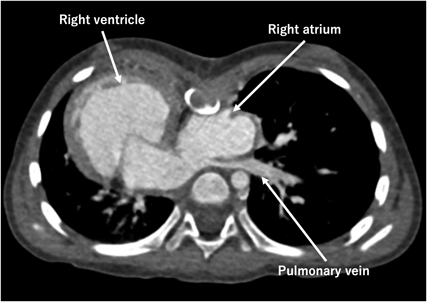

Preoperative computed tomography scan revealed compression of the right atrium and the left pulmonary vein by a depressed sternum, with the Haller Index of 6.25 (Fig. 1).

In our case, simultaneous repair was considered necessary to secure the Fontan pathway by correcting the pectus excavatum; compression to the Fontan route and the pulmonary veins were avoided. As anticipated preoperatively, postoperative CT revealed that the Fontan conduit occupied a considerable space within the thoracic cavity. The pulmonary veins appear better structured than preoperative state.